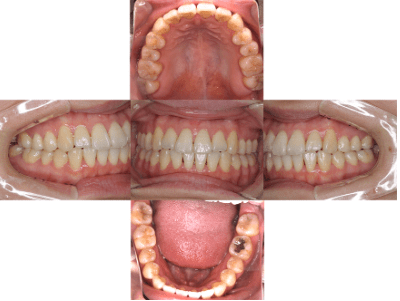

治療前

• 初診時年齢:25歳

• 主訴:開咬

• 診断:舌癖を伴う歯性の開咬、非抜歯

• 治療内容:下で前歯を押してしまい、前歯で咬めない状態でした。マウスピース型カスタムメイド矯正歯科装置(製品名インビザライン 完成物薬機法対象外)で、奥歯を低くしつつ、前歯を伸ばし、前歯で咬めるようになりました。

• 治療期間:2年6ヶ月

• リスク:ブラックトライアングル(歯と歯の間と歯ぐきの間の三角形の隙間)が強くでる場合がある

• 費用:90万円